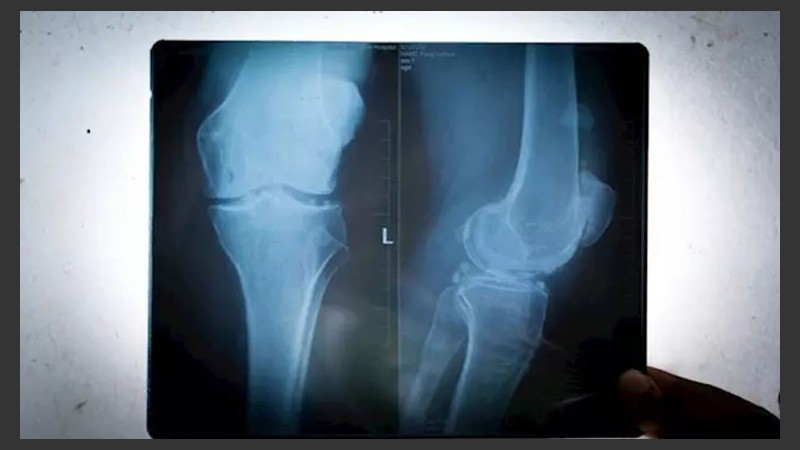

De 1918 a 2018 se triplicó el número de rodillas humanas que lucían fabelas, aparentemente inútiles, ya que son pequeños huesos enterrados en el tendón detrás de algunas rodillas, según publica el 'Journal of Anatomy' y reproduce Infosalus.

Para este nuevo estudio los científicos utilizaron 66 trabajos de investigación que abarcaban 27 países y 21.676 rodillas individuales. Esto incluyó estudios que identifican la fabela por rayos X y también por disección.